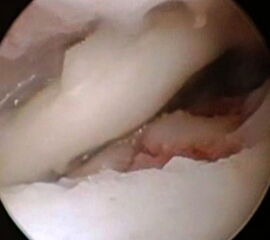

Arthroskopie

Die arthroskopische Diagnostik bietet gegenüber den rein bildgebenden Methoden den Vorteil, dass der Defektbereich auch mit einem Tasthaken palpatorisch untersucht werden kann. Dadurch kann die Defektgröße bestimmt und eine evtl. Instabilität eines osteochondralen Fragmentes festgestellt werden 28. Der Nachteil ist dabei allerdings, dass eine genaue Beurteilung des subchondralen Knochens nur bedingt erfolgen kann.

Bei chondralen Läsionen III-IV° oder bei osteochondralen Läsionen (≥ Stadium 2) mit Kontinuitätsunterbrechung der Knorpeloberfläche und Instabilität des Fragmentes (Abb. 11), besteht in der Regel die Indikation zum Debridement und Kürettage der Läsion und Anwendung von knochenmarkstimulierenden Techniken wie der Anbohrung oder Mikrofrakturierung. Durch die chirurgische Eröffnung des subchondralen Knochens sollen über die gesetzten Blutungsherde pluripotente mesenchymale Stammzellen in die Defektzone gelangen und einen Reparaturprozess einleiten 52. Ziel ist die Bildung eines möglichst belastungsstabilen Ersatzknorpelgewebes. Das arthroskopische Vorgehen mit Knochenmarkstimulation stellt nach einem Expertenkonsensus während der „Conference of the International Society of Arthroscopy, Knee Surgery and Orthopaedic Sports Medicine and International Federation of Sports Medicine (ISAKOS—FIMS)” aus dem Jahre 2005 für die meisten Fälle die Methode der ersten Wahl dar 39. Bevorzugt wird heute meist die Mikrofrakturierung, bei der rein arthroskopisch nach Stabilisierung der Läsion mit Schaffung intakter Knorpelkanten mit verschieden abgewinkelten Ahlen multiple Löcher unter Erhalt von Knochenbrücken in das Defektbett geschlagen (Abb. 12 und 13) und so eine Verbindungen zum spongiösen Knochen hergestellt wird. In der Regel können die Läsionen mit den arthroskopischen Standardportalen behandelt werden 5354. Orientierend kann bei der Planung und physiologischer uneingeschränkter Plantarflexionsmöglichkeit angenommen werden, dass neben den anterioren Defekten auch Läsionen, welche die vordere Hälfte des posterioren Anteil des Talus betreffen, erreicht und rein arthroskopisch behandelt werden können 39. Im Zweifelsfall kann eine Bildgebung in maximaler Plantarflexion weitere Hinweise geben.